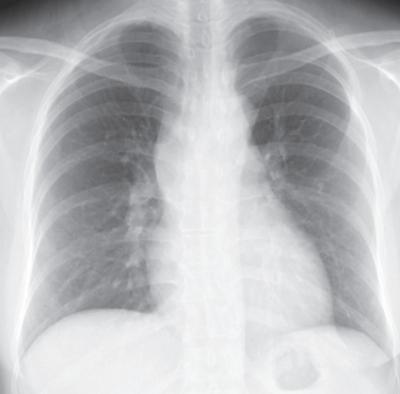

34歳の女性。前胸部痛を主訴に来院した。3か月前から前胸部痛が出現し徐々に増強してきた。体温36.8℃。血圧118/64mmHg。SpO2 98%(room air)。心音と呼吸音に異常を認めない。胸部エックス線写真と胸部造影CTとを別に示す。

考えられる疾患はどれか。2つ選べ。

a. 胸腺腫

b. 神経鞘腫

c. 心膜嚢胞

d. 胸膜中皮腫

e. 悪性リンパ腫